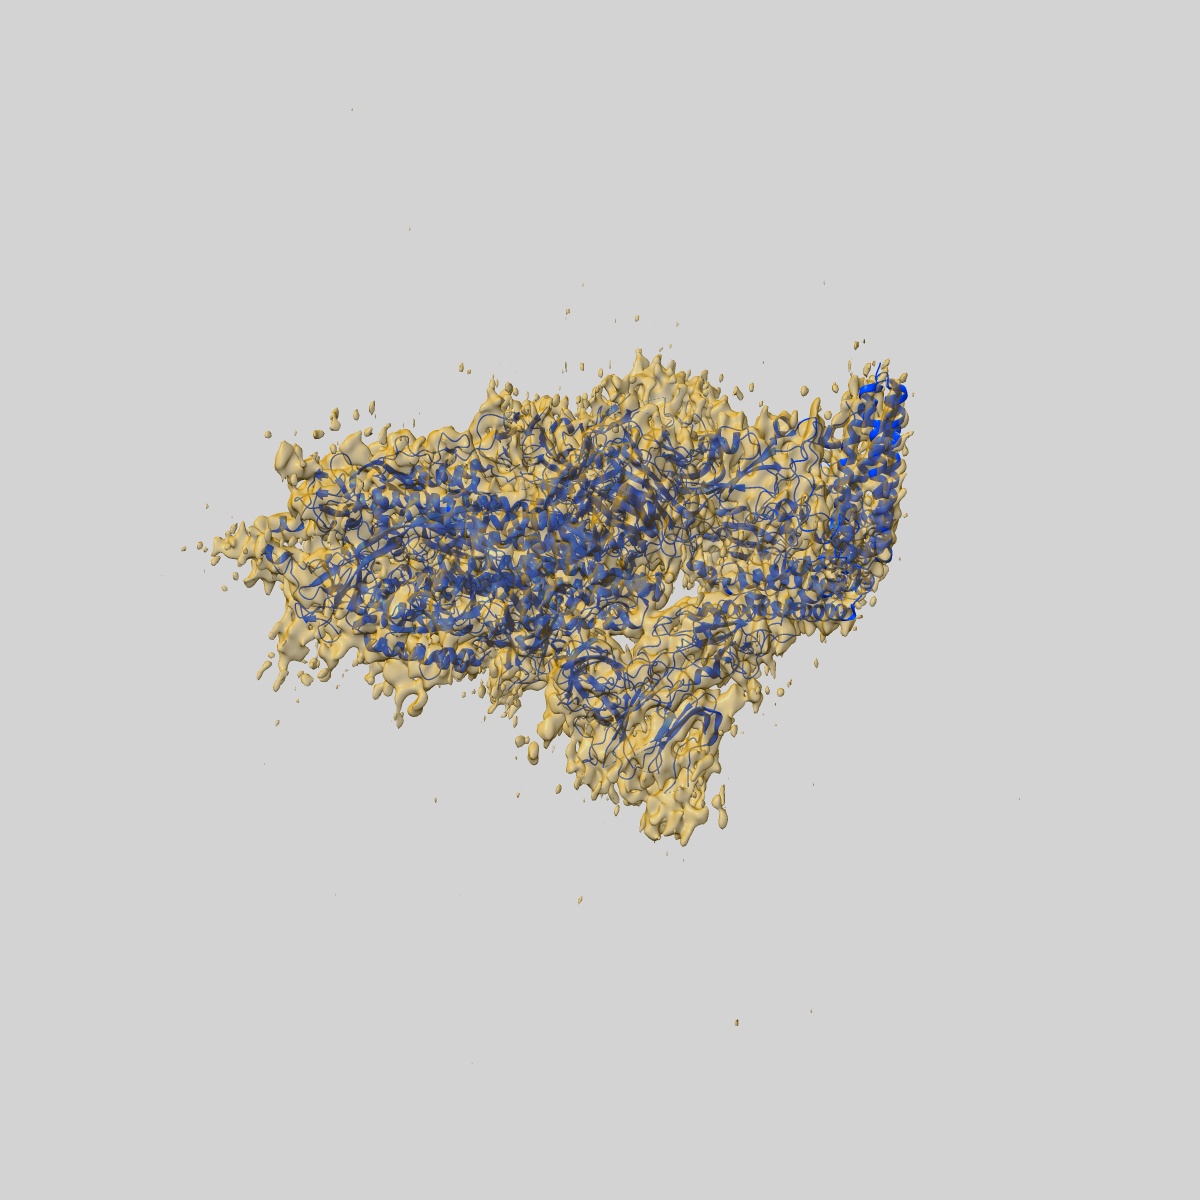

EMD-22916

Structure of the SARS-CoV-2 S 6P trimer in complex with the ACE2 protein decoy, CTC-445.2 (State 4)

Single-particle4.1 Å

Sample: Ternary complex of CTC445.2 inhibitor with SARS-CoV-2 S 6P glycoprotin

Fitted models: 7kl9